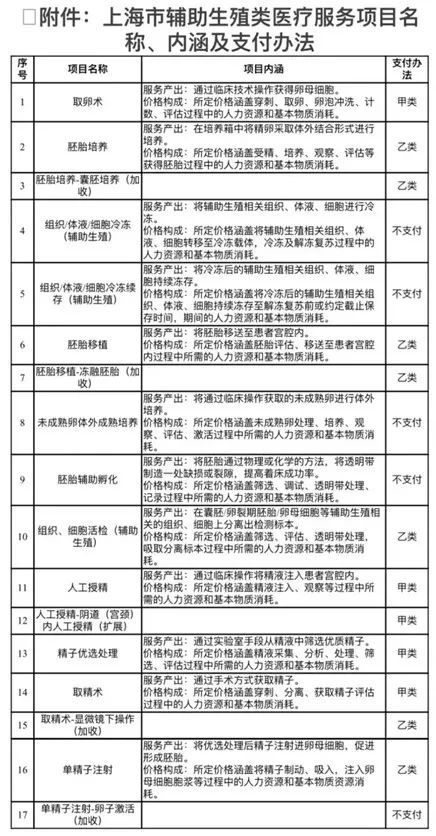

转自:上海市普陀区人民政府网站